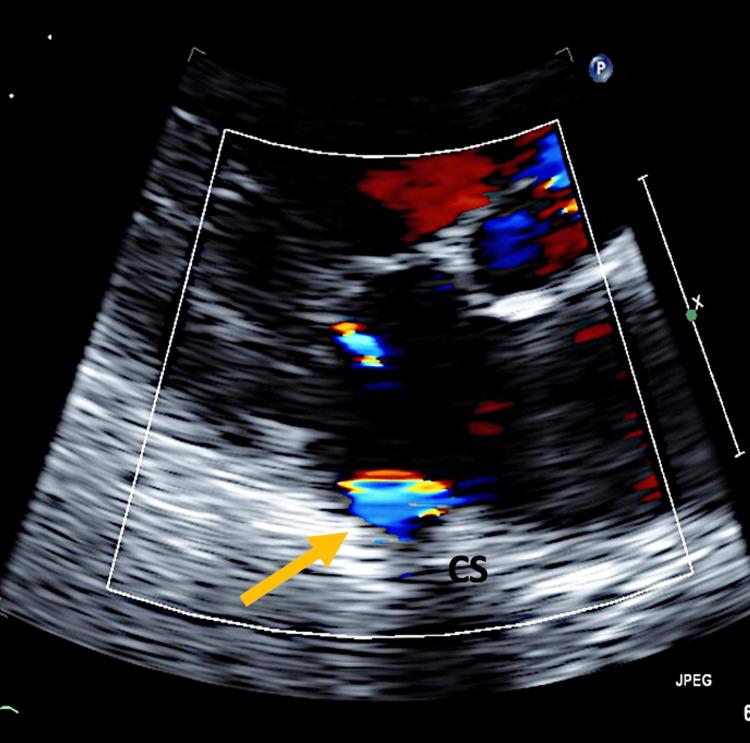

Coronary artery fistulas (CAFs) are rare vascular anomalies characterized by abnormal connections between coronary arteries and cardiac chambers or adjacent structures. Advances in cardiac interventions have led to an increasing recognition of acquired CAFs, which are typically congenital. We present a case of a 62-year-old male with a complex medical history, including hypertension, atrial fibrillation, and heart failure, who presented with exertional chest pain and palpitations. Diagnostic evaluation revealed a significant CAF originating from the right coronary artery (RCA) and terminating into the coronary sinus and right ventricle. Despite the absence of significant coronary artery occlusions, the fistula was deemed clinically significant due to its potential to cause myocardial ischemia. Management involved guideline-directed medical therapy and lifestyle modifications. This case underscores the importance of early recognition and appropriate management of CAFs to optimize patient outcomes. Further research is needed to better understand the natural history and optimal management strategies of CAFs.

冠状动脉瘘(CAFs)是一种罕见的血管异常,其特征是冠状动脉与心腔或相邻结构之间存在异常连接。心脏介入技术的进步使得人们越来越认识到获得性CAFs,而CAFs通常是先天性的。我们报告一例62岁男性病例,其有复杂的病史,包括高血压、心房颤动和心力衰竭,表现为劳力性胸痛和心悸。诊断评估发现一个源自右冠状动脉(RCA)并终止于冠状窦和右心室的大型冠状动脉瘘。尽管没有明显的冠状动脉闭塞,但由于该瘘管有导致心肌缺血的可能性,故被认为具有临床意义。治疗包括遵循指南的药物治疗和生活方式改变。该病例强调了早期识别和适当管理冠状动脉瘘以优化患者预后的重要性。需要进一步研究以更好地了解冠状动脉瘘的自然病程和最佳管理策略。